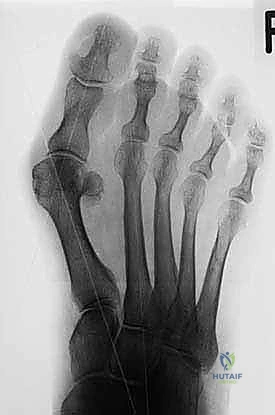

2. التقييم الشعاعي (Radiographic Evaluation)

تعتبر الأشعة السينية (X-rays) حجر الزاوية في التخطيط لعملية شيفرون البعيدة. يطلب الدكتور هطيف صور أشعة بوضعيات محددة (أمامية خلفية، وجانبية) أثناء وقوف المريض وتحميل وزن جسمه على قدميه (Weight-bearing X-rays). هذا أمر بالغ الأهمية لأن التشوه يظهر بحجمه الحقيقي فقط تحت تأثير وزن الجسم.

من خلال هذه الصور، يقوم الدكتور هطيف بقياس زوايا حاسمة تحدد نوع الجراحة المطلوبة:

* زاوية إبهام القدم الأروح (Hallux Valgus Angle - HVA): هي الزاوية بين المحور الطولي لعظم المشط الأول والمحور الطولي للسلامية الدانية. الزاوية الطبيعية أقل من 15 درجة. في الحالات الخفيفة إلى المتوسطة (التي تناسبها عملية شيفرون)، تتراوح بين 15 إلى 40 درجة.

* الزاوية بين أمشاط القدم (Intermetatarsal Angle - IMA): هي الزاوية بين المحور الطولي لعظم المشط الأول وعظم المشط الثاني. الزاوية الطبيعية أقل من 9 درجات. عملية شيفرون البعيدة مثالية عندما تكون هذه الزاوية بين 9 و 15 درجة.

* تقييم مفصل (DMAA - Distal Metatarsal Articular Angle): لتقييم ميلان السطح المفصلي.

* موقع العظام السمسمية: تقييم مدى انزياحها عن مسارها الطبيعي.

* وجود التهاب مفاصل تنكسي (خشونة): فحص تآكل الغضاريف، حيث أن وجود خشونة شديدة قد يغير خطة العلاج من عملية شيفرون إلى عملية دمج المفصل (Arthrodesis).